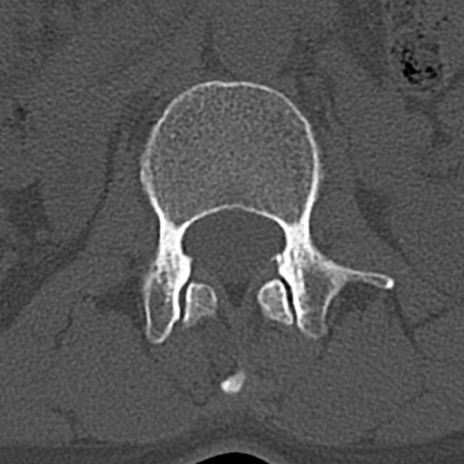

【整形】TIPS症例4 腰椎CT(横断像)

腰椎CT

横断像と矢状断像